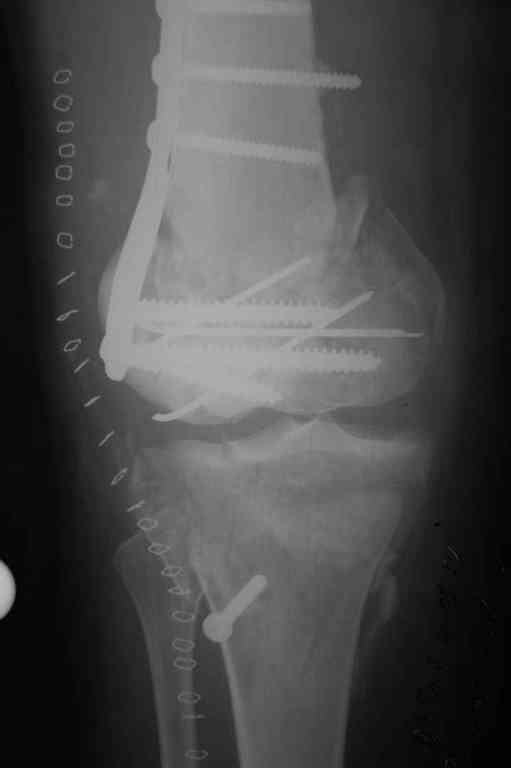

Re: Последствия открытого перелома дистального отдела бедра

Пожалуйста, снимки.